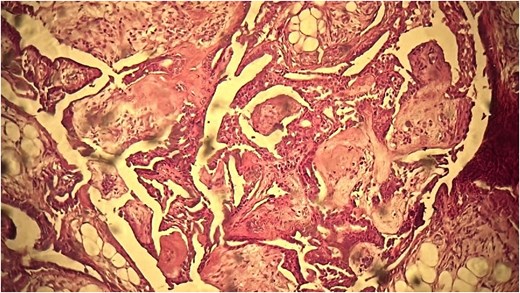

A 62-year-old Moroccan man, with no significant medical history, presented with a cheek swelling evolving over 9 months without associated symptoms. Clinical examination revealed a 1.2 cm nodular swelling in the cheek. It was mobile and skin-colored, without inflammatory signs. Lymph nodes and salivary glands were normal. An excisional biopsy of the mass was performed. Macroscopically, it was a 1.2 cm beige, friable to firm, rounded nodule. Microscopic examination showed a well-circumscribed benign tumor proliferation composed of cysts, tubules, and ducts, lined by a bilayered epithelium. The cells exhibited no nuclear atypia. The fibromyxoid and chondroid stroma (Fig. 4) allowed for diagnosis without additional techniques. There was no perineural invasion or vascular emboli, and surgical margins were clear. Postoperative recovery was uneventful, and no further follow-up or additional examinations were necessary.